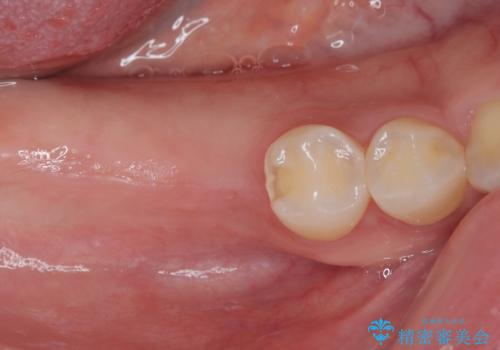

スペースが整った段階で、右下の第一大臼歯と第二大臼歯にインプラントを埋入。

その後、挺出していた右上第一大臼歯と第二大臼歯に装着されていた銀歯についても、審美性と適合性の向上を目的に、オールセラミッククラウンにやり替えました。

これにより、より自然で美しい見た目と、高い精度の咬合が得られています。